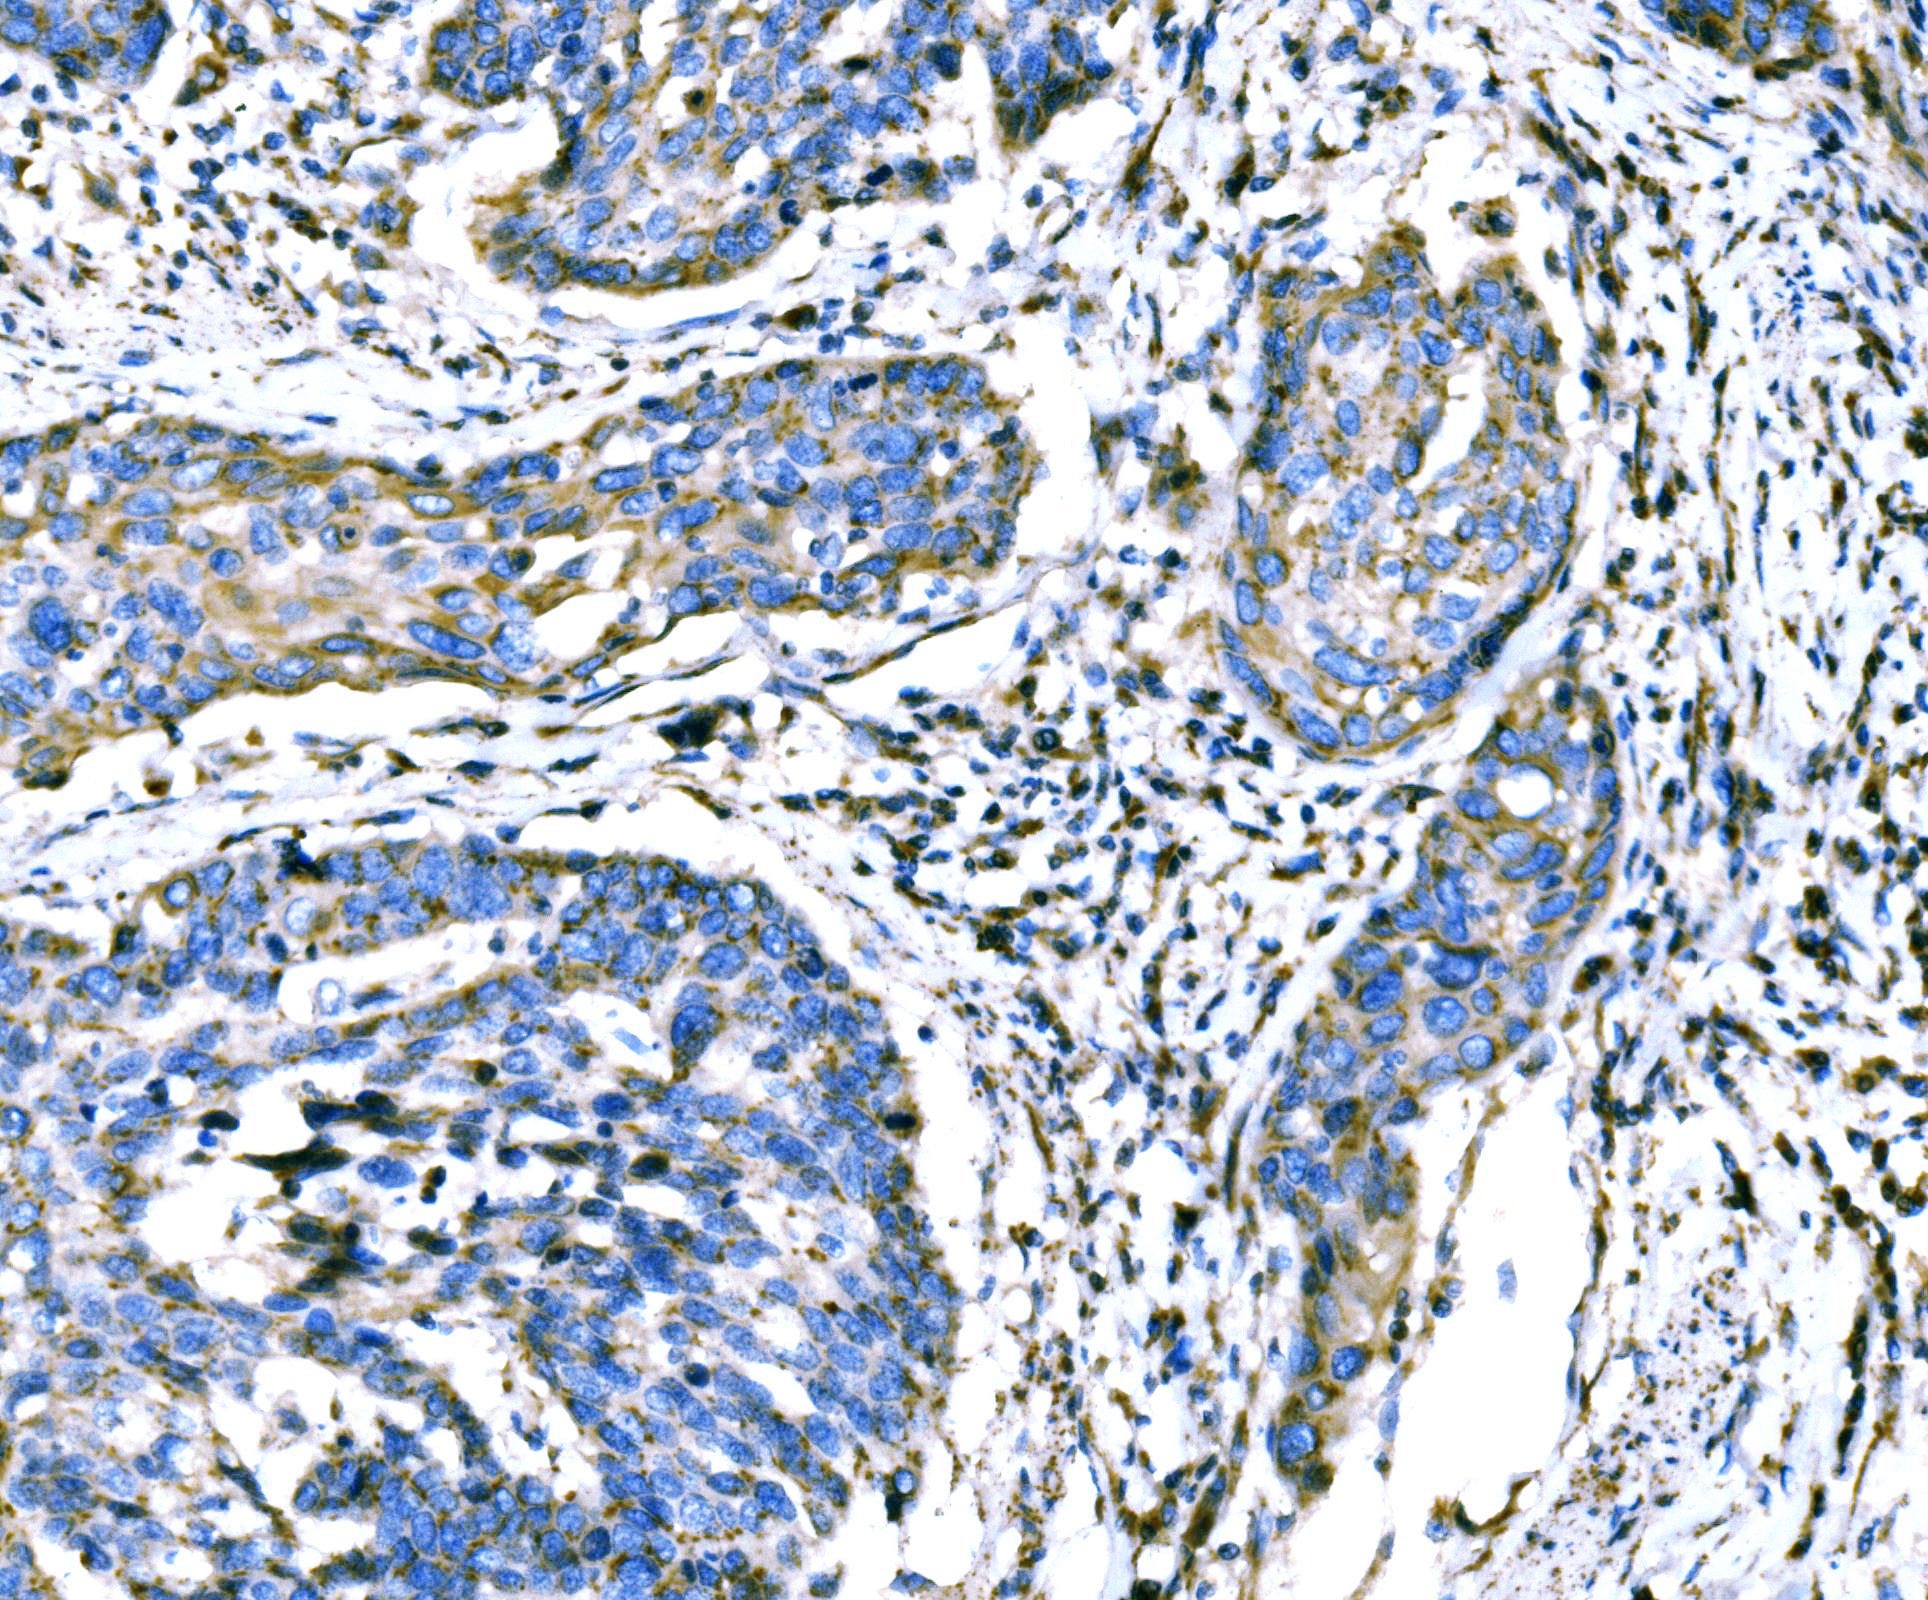

IHC analysis of ATG16L1 using anti-ATG16L1 antibody (A00526-3).

ATG16L1 was detected in a paraffin-embedded section of human esophageal squamous carcinoma tissue. Biotinylated goat anti-rabbit IgG was used as secondary antibody. The tissue section was incubated with rabbit anti-ATG16L1 Antibody (A00526-3) at a dilution of 1:200 and developed using Strepavidin-Biotin-Complex (SABC) (Catalog # SA1022) with DAB (Catalog # AR1027) as the chromogen.